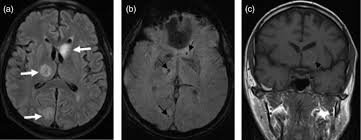

Σε αυτή την περίπτωση, μαζί με το πρήξιμο, ο ασθενής ανέπτυξε κύστες και στις δύο πλευρές του εγκεφάλου του. Διαπιστώθηκε αργότερα ότι ήταν ο ταινιοσκώληκας, που είχε εναποθέσει αυγά μέσα στον εγκέφαλο του άνδρα.

Του χορηγήθηκε θεραπεία με το φάρμακο αλβενδαζόλη, η οποία οδήγησε σε βελτίωση δύο εβδομάδες αργότερα.